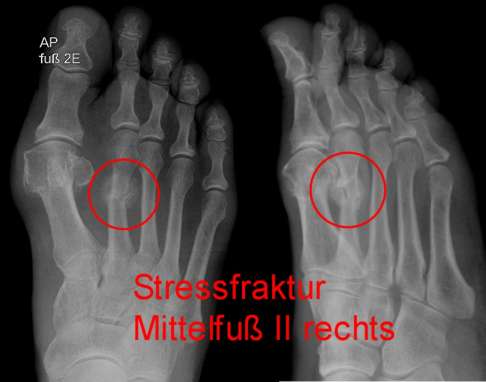

Ein typisches Beispiel für einen Patienten mit Ermüdungsbruch ist ein Laufsportler, der seinen Trainingsumfang wegen eines bevorstehenden Wettkampfes deutlich steigert. Körperliche Ausdauer, Muskelkraft und Kreislauf sind dem gesteigerten Trainingspensum des Athleten gewachsen, dagegen passen sich Sehnen und Knochen nur langsam an. Plötzlich verspürt der Läufer ziehende Schmerzen im Mittelfuß. In diesem Fall zieht der Fußspezialist einen Ermüdungsbruch in Erwägung. Unterstützt wird er von bildgebenden Untersuchungen, die typische Veränderungen – häufig am Mittelfuß – zeigen: Zunächst sind Knochenödeme (Wassereinlagerungen) sichtbar, später ist die Stressreaktion auch an der geschädigten Knochensubstanz erkennbar.

Bildgebende Untersuchung: Röntgen, CT, MRT

Nach der klinischen Untersuchung veranlasst der Arzt ein bildgebendes Verfahren, um die Situation der Knochen, Muskeln und Bänder beurteilen zu können. Die Diagnosesicherung ist dabei nicht immer leicht, da sich Knochenveränderungen durch Stressfrakturen im Anfangsstadium sehr variabel äußern. Röntgenbilder sind häufig nicht aussagekräftig. Meist sind erst zwei bis vier Wochen nach dem Auftreten erster Beschwerden feine Unterbrechungen der Knochenstruktur im Röntgen sichtbar. Erst später können Knochenverdichtungen, Bruchlinien oder Knochenhautreaktionen auftreten. Deshalb muss der behandelnde Arzt die Diskrepanz zwischen klinischen Beschwerden und einem noch unauffälligen Befund beachten, um bereits im Anfangsstadium die Diagnose Ermüdungsbruch stellen zu können.